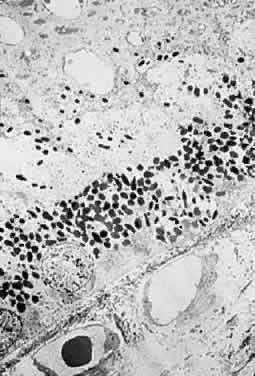

PATHOLOGIC FINDINGS

Clinicopathologic correlations of photic retinopathy have been reported by several investigators.16,75,76,144–146 Aware of prior studies by others on rats,25,147–150, Tso and coauthors reported the first of their series, performed on monkeys in 1972.75 They believed that the difference in their observations versus those published on rats might be related to the species of animal studied. Tso and coworkers created a model of chronic photic maculopathy through exposure to an indirect ophthalmoscope and found that significant changes were produced the first week after exposure, but a distinct maculopathy became evident only after an extended follow-up (5 months). They also described three stages in which this maculopathy occurs: initial degeneration in the first week, macrophagic response between the first week and first month, and repair and regeneration between the first and fifth month. Tso and associates also noted that, in the reparative phase, scarlike lesions noted clinically corresponded to proliferation of the RPE on a cellular level and, despite changes in the RPE, the overlying photoreceptors had regenerated. These clinicopathologic correlations led to more studies of macular response to light-induced injury. Histopathologic study of photic retinopathy in the human eye caused by exposure to light from the operating room microscope was reported by Green and Robertson in 1991.144 They describe the light and electron microscope findings of operating room microscope-induced maculopathy in a patient's eye after exposure to the light source for 60 minutes, 72 hours before enucleation for an iris melanoma (Figs 5 through 8). Findings in this acute form of photic retinopathy occurred mainly at the level of the RPE and photoreceptor layer and included the following: localized necrosis of the RPE; loss of the apical villi, plasma membranes, and cytoplasmic organelles of the RPE cells; extrusion of the retinal pigment epithelial pigment granules; and extensive disruption of the outer lamellae of the photoreceptors. Swollen mitochondria were present within the photoreceptor inner segments. Although this study was designed to address the issue of acute light-induced retinal damage, the additional finding of thinned retinal pigment epithelial cells, which apparently had migrated under injured RPE cells, suggests that a reparative process had already begun. The findings of Green and Robertson are consistent with those of Jaffe and coworkers reported in primates.146

Fig. 7. Electron-microscopic view of photic retinopathy with extensive derangement of the outer segments of the photoreceptors with distention (main figure), distortion, compaction, partial disintegration of the lamellar disks and disruption of plasma membranes. The inner segments of the cones are moderately swollen and the mitochondria are markedly distended. Inset shows details of the swollen mitochondria. (Green WR, Robertson DM: Pathologic findings of photic retinopathy in the human eye. Am J Ophthalmol 112:520, 1991)

Fig. 8. Electron-microscopic view of photic retinopathy. The retinal pigment epithelial cells are severely damaged with loss of plasma membranes, apical villous processes, basal infoldings and extrusion of pigment granules. Overlying the retinal pigment epithelial cells, a variably dense granular material containing fragments of outer segments is observed. (Green WR, Robertson DM: Pathologic findings of photic retinopathy in the human eye. Am J Ophthalmol 112:520, 1991)